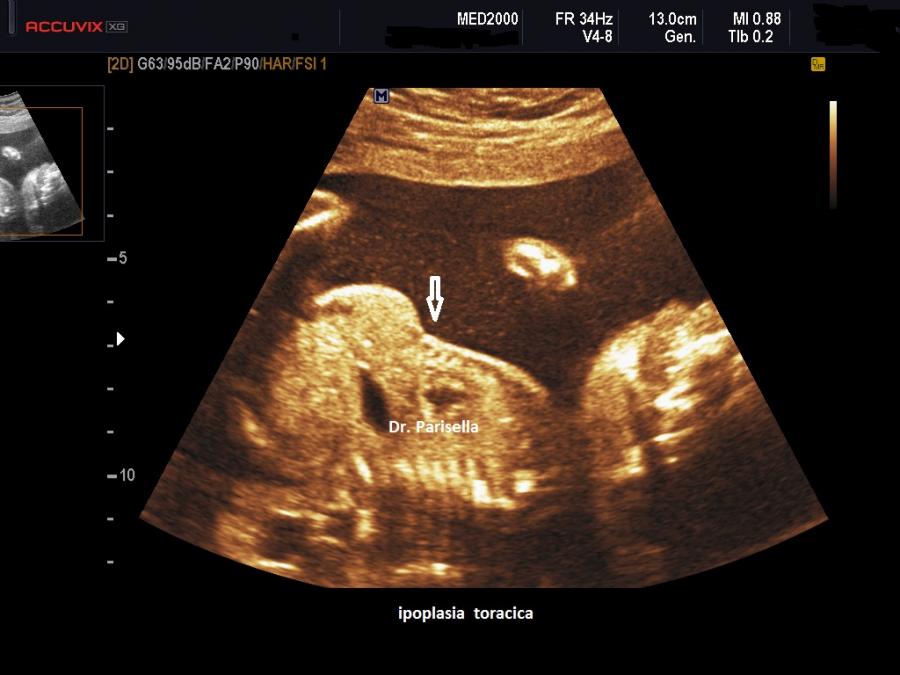

All'ecografia prenatale si riscontra ipoplasia toracica (torace stretto e coste corte), rizomelia lieve-moderata e frequentemente  displasia renale policistica.

Essendo la brevità degli arti frequentemente modesta la diagnosi prenatale è difficoltosa prima del terzo trimestre e comunque non può essere fatta prima della 24a settimana di gestazione.